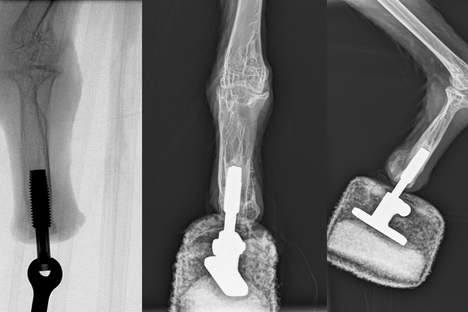

X-ray shows the prosthesis inserted in the right paw of the bird Mia (Photo: Medical University of Vienna)

This new technique is known as osseointegration and Aszmann's working group recently used it for the first time in Austria on a patient who had lost an arm – however, it had never previously been attempted on a bird. In osseointegration, external parts of the prosthesis are directly connected to a bone anchor to guarantee a solid skeletal attachment. Aszmann explains: "This concept offers a high degree of embodiment, since osseoperception provides direct intuitive feedback, thereby allowing natural use of the extremity for walking and feeding. For the first time we have now successfully bionically reconstructed the limb of a vulture."

The operation on the bearded vulture was successfully carried out, together with Rickard Branemark from the Center for Osseointegration Research (San Francisco), at the Center for Biomechanical Research at MedUni Vienna (Director: Bruno Podesser). Rehabilitation and prosthetic treatment took place back in Haringsee. "The bird made the first attempts to walk after just three weeks and the prosthesis was under full load after six weeks. Today the bearded vulture can once again land and walk using both feet, making it the first 'bionic bird'," says Aszmann, who is famous throughout the world for his ground-breaking work on bionic hands.